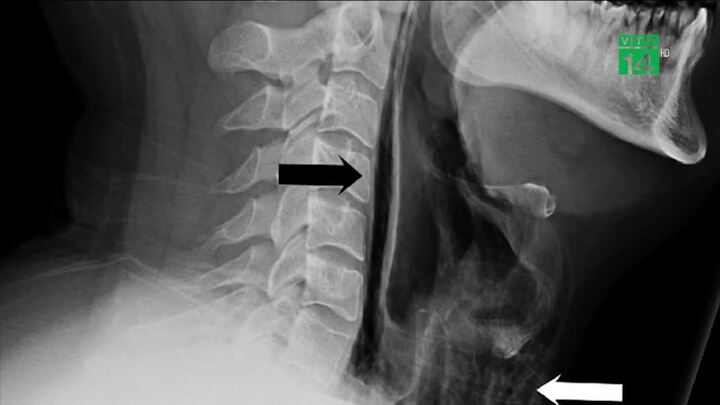

Các nhà khoa học cho biết việc cố nhịn hắt xì hơi có thể khiến vỡ cổ họng, thủng màng nhĩ, vỡ mạch máu não giống như một người đàn ông Anh vừa gặp phải.